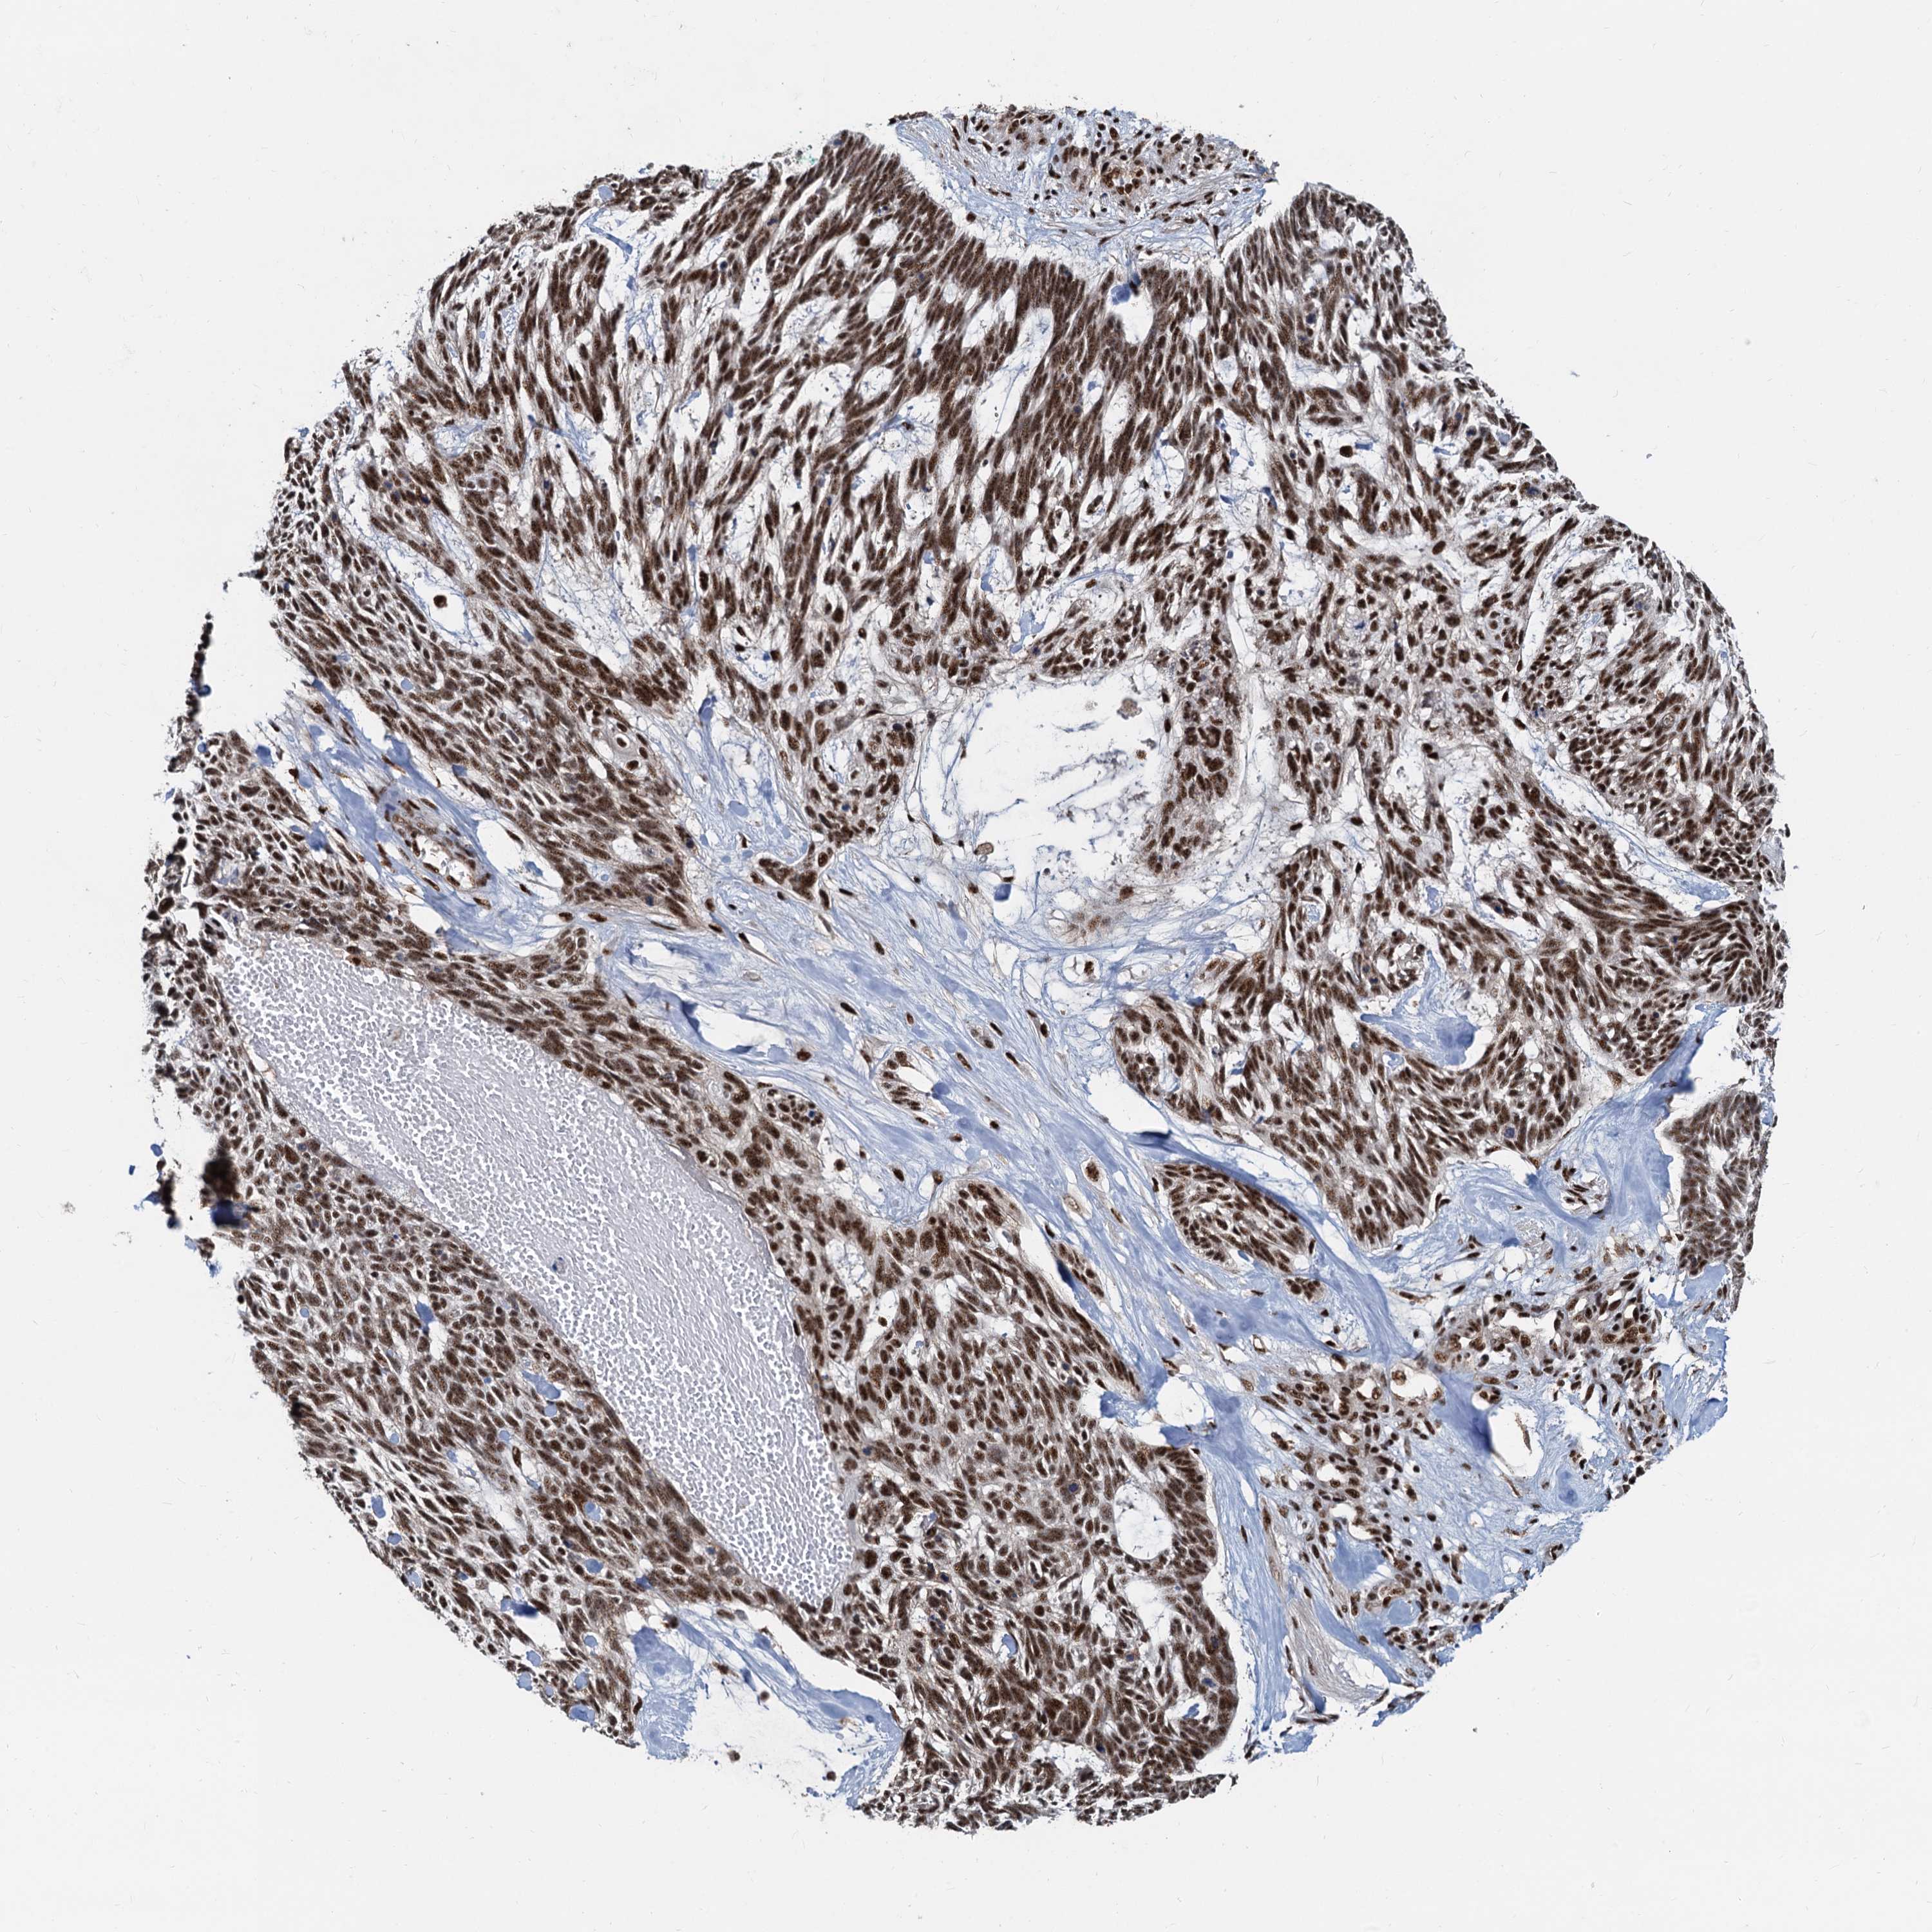

SKIN CANCER - Protein expressioni

A mouse-over function shows sample information and annotation data. Click on an image to view it in a full screen mode. Samples can be filtered based on level of antibody staining by selecting one or several of the following categories: high, medium, low and not detected. The assay and annotation is described here.

Antibody stainingi

Antibody staining in the annotated cell types in the current human tissue is reported as not detected, low, medium, or high, based on conventional immunohistochemistry profiling in selected tissues. This score is based on the combination of the staining intensity and fraction of stained cells.

Each image is clickable and will lead to virtual microscopy that enables deeper exploration of all samples and also displays staining intensity scores, fraction scores and subcellular localization as well as patient and tissue information for each sample.

Antibody HPA040252

Staining

High

Medium

Low

Not detected

Intensity

Strong

Moderate

Weak

Negative

Quantity

>75%

75%-25%

<25%

None

Location

Nuclear

Cytoplasmic/membranous

Cytoplasmic/membranous,nuclear

Basal cell carcinoma

Squamous cell carcinoma, NOS

Squamous cell carcinoma, metastatic, NOS